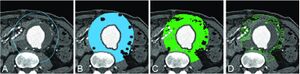

Outer Wall Segmentation of Abdominal Aortic Aneurysm by Variable Neighborhood Search Through Intensity and Gradient Spaces

Publication: J Digit Imaging. 2018 Aug;31(4):490-504. PMID: 29352385 | PDF Authors: Siriapisith T, Kusakunniran W, Haddawy P2. Institution: Department Radiology, Faculty of Medicine Siriraj Hospital, Mahidol University, Bangkok, Thailand. Abstract: Aortic aneurysm segmentation remains a challenge. Manual segmentation is a time-consuming process which is not practical for routine use. To address this limitation, several automated segmentation techniques for aortic aneurysm have been developed, such as edge detection-based methods, partial differential equation methods, and graph partitioning methods. However, automatic segmentation of aortic aneurysm is difficult due to high pixel similarity to adjacent tissue and a lack of color information in the medical image, preventing previous work from being applicable to difficult cases. This paper uses uses a variable neighborhood search that alternates between intensity-based and gradient-based segmentation techniques. By alternating between intensity and gradient spaces, the search can escape from local optima of each space. The experimental results demonstrate that the proposed method outperforms the other existing segmentation methods in the literature, based on measurements of dice similarity coefficient and jaccard similarity coefficient at the pixel level. In addition, it is shown to perform well for cases that are difficult to segment. "Ground truth segmentations were also obtained by manual segmentation with the 3D Slicer version 4.7.0." |

An example of graph cut with probability density function corresponding to the diagram in Fig. 5. a. The initial contour for the segmentation. b. The label region with bone and air removal. For the graph construction, each pixel in the region is represented by a node in the graph. c. The output label region of segmentation using max-flow/min-cut algorithm. d. The output contour of segmentation corresponds to the outer boundary of c. |